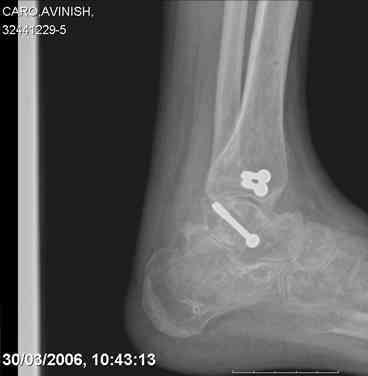

ya by popytalsya sobrat talus anatomichno,seichas pozdno operirovat

iz za oteka,po etomy distrakziya apparatom budet optmalna.Posyalu vam

podobyai moi sluchai.